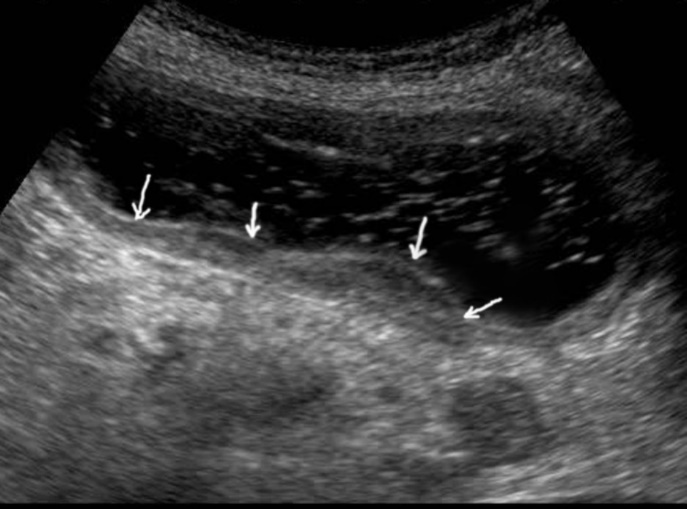

T3 stage of polypoid form was recorded in one case, ulcerative form – in 11 cases, infiltrative ulcerative forms – in 21 cases and diffused infiltrative forms – in 8 cases. The Sonographic features of infiltrative ulcerative form of gastric carcinoma was shown as local uneven thickening of the stomach wall with a length of up to several centimeters with intermittent images and ulceration of the mucosa (Figure 11). The Ulcerative form of gastric carcinoma was shown as a raised margins surrounded by a thickened gastric wall with irregular margins (Figure 12). Gastric carcinomas of diffuse infiltrative form is illustrated as a diffuse thickening of the muscle layer, a smooth contour, discontinuous mucosal image without ulceration and involvement of the serous membrane in the process (Figure 13).

Figure 13.Gastric carcinomas of diffuse infiltrative form in the posterior wall of the stomach body of stage T3. The tumor is manifested by diffuse thickening of the muscle layer, a smooth contour, discontinuous mucosal image without ulceration and involvement of the serous membrane in the process. An enlarged, altered lymph node of low echogenicity, round shape, without differentiation of the peripheral and central part, is visualized behind the stomach.